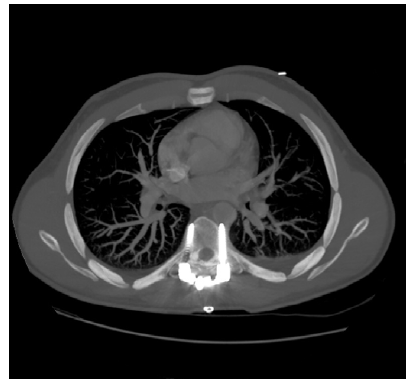

Doente de 27 anos, sexo masculino, independente nas atividades de vida diária, jogador profissional de andebol, com antecedentes pessoais de tabagismo ativo (15 cigarros/dia), sem patologias de relevo ou medicação de ambulatório. Iniciou dificuldade para a marcha com quadro clínico caracterizado por "falha das pernas" (sic) durante os treinos de andebol, tendo sido internado no serviço de Neurologia do Hospital de Setúbal para melhor caracterização. Teve alta para posterior avaliação pela Neurocirurgia. Denotou agravamento diário da marcha que se tornou possível apenas com o suporte de terceiros. Negava dor axial ou sintomas B. Clinicamente apresentava: hiperreflexia dos membros inferiores com discreta espasticidade; hipostesia álgica no território T8; reflexo cutâneo plantar indiferente; Romberg com desequilíbrio marcado; marcha parético-espástica de base larga e apenas possível com apoio de terceiros ou apoio, fracamente limitada pelo défice propriocetivo. Realizou TC que revelou: lesão óssea de T6 caracterizada por marcada trabeculação óssea com aparente extensão intra-canalar. Sem evidência de fraturas.

Realizou então ressonância magnética que mostrava captação de contraste em toda a estrutura óssea de T6 associado a lesão intra-canalar (hemangioma ósseo vertebral Frankel D) associada a marcada compressão medular. Analiticamente não apresentava alterações de relevo. Foi medicado com Dexametasona 10 mg e programou-se cirurgia urgente, tendo sido submetido a vertebroplastia + laminectomia de T5, T6 e parcial T7 com remoção de massa epidural, e colocação de 8 parafusos transpediculares T4-T5-T7-T8.

A protrusão acetabular é caracterizada por deformidade da parede medial do acetábulo com migração progressiva da cabeça femoral para o interior da pelve, causando distúrbios mecânicos, dor e importante limitação funcional da articulação da anca. Quanto à etiologia é classificada em primária (75,3%) ou secundária (24,7%) e, de acordo com parâmetros radiológicos em leve, moderada e grave.4 A forma primária ou protrusão essencial geralmente é bilateral e há dificuldades no seu diagnóstico, devido aos sintomas serem mínimos ou ausentes. No caso clínico descrito, poderá tratar-se de uma forma secundária, se tiver resultado de complicação da cirurgia anterior, contudo desconhece-se o estado prévio. O índice Tornozelo-Braço ou índice de pressão arterial é uma ferramenta útil, em conjunto com a observação física.5 Um índice <0,9 tem sensibilidade de 87% e especificidade de 97% na avaliação do trauma vascular, atingindo uma sensibilidade de 95% a propósito dos troncos arteriais grandes. Um índice >0,9 sem sinais de lesão ortopédica permite referenciar o doente para nova observação nos próximos dias, para eventual apresentação tardia de lesão vascular. Na contusão, o local mais frequente de lesão é a aorta descendente desde o óstio da artéria subclávia até ao ligamento aórtico. Na maioria dos casos ocorre rotura da íntima, que poderá levar ao desenvolvimento de uma dissecção aórtica aguda. A angio-TC permite diagnosticar uma lesão da aorta torácica com grande acuidade e tornou-se standard nos traumas torácicos. Se não houver possibilidade de se realizar a angioTC, a ecografia transesofágica pode ser usada, embora de forma limitada.1